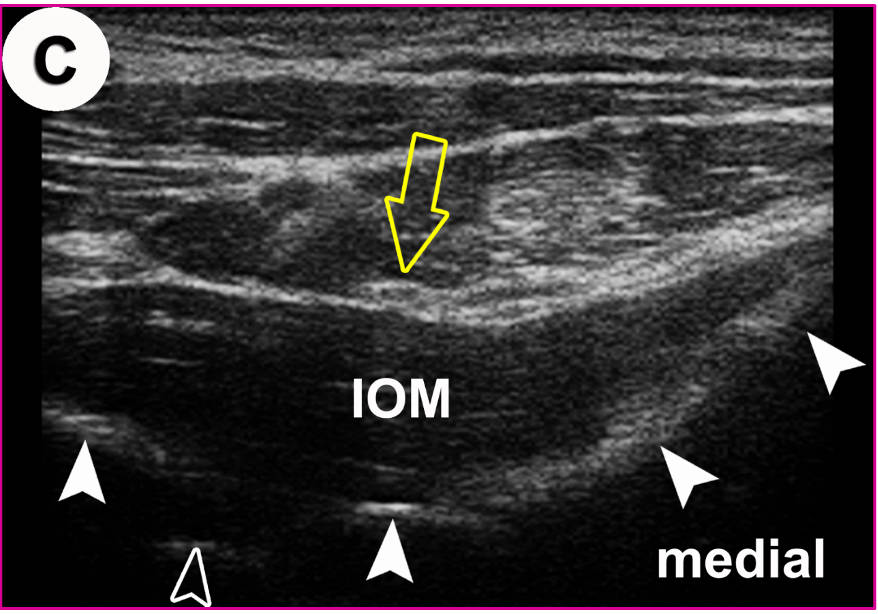

US-Darstellung und experimentelle Blockade (Pfeilköpfe: Nadel) des N. cutaneus femoris lateralis an einer Körperspenderin. Mittlerweile gängige Anwendung in der Regionalanästhesie und Schmerztherapie

Der hell erscheinende N. cutaneus femoris lateralis (Pfeil) wird am Oberschenkel in seinem „fettgefüllten Flachtunnel“ (im US dunkel!) am leichtesten aufgefunden: “POV“ (Point of Optimal Visibility) nach Prof. Moriggl.